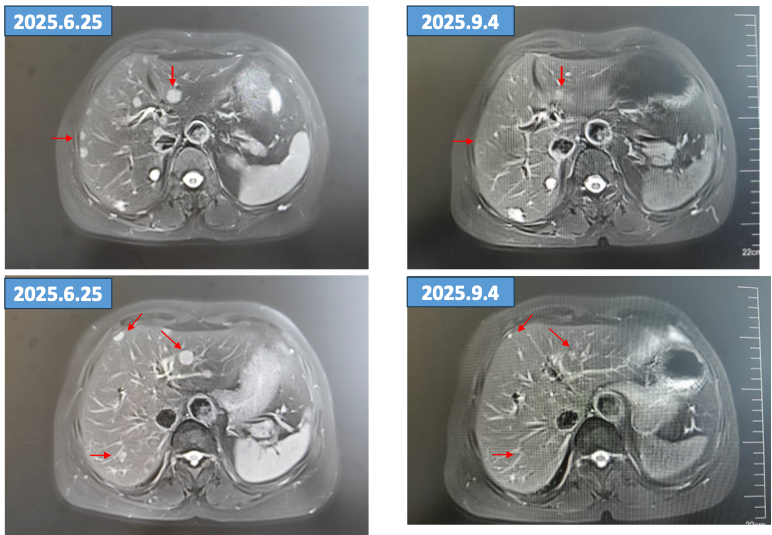

用药2个月后(2025年9月4日)复查肝脏磁共振,病灶较基线(2025年6月25日)明显缩小,疗效评估为PR 。

5.png